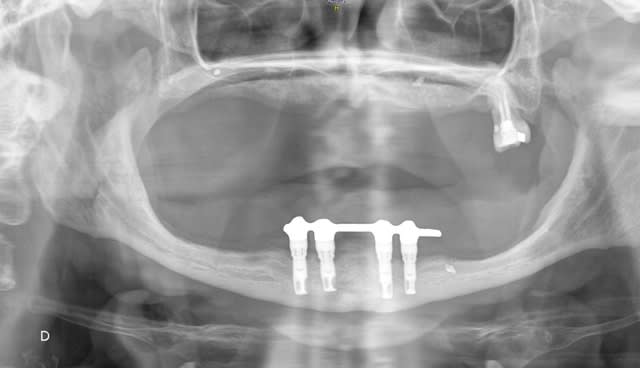

voici le cas :

Patiente qui se présente pour sa PAC inf qui bascule et la blesse en secteur 3.

Les implants et la barre ont été posé il y a 10 ans.

L'extension droite de la barre est cassée depuis environ 2 ans.

çà ressemble à du nobel MK hex externe

y a de fortes chances que la barre soit en précieux ou 1/2 précieux

- "les implants sont suédois" me dit-elle. La pano semble lui donner raison, mais je suis pas expert !

- la barre ? on dirait de l'or.

en effet c est des MKIII HEX externe (j en utilise encore pour ce genre de cas ) avec vraisemblablement des multiunits